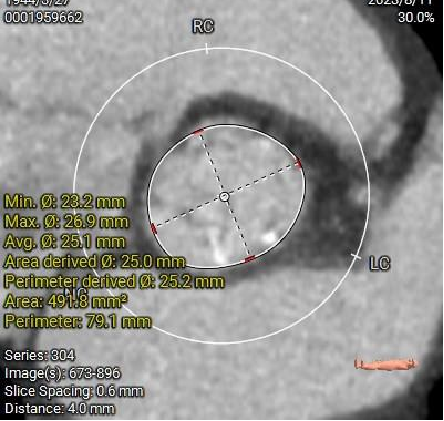

主动脉根部径线:

多平面分析:

LVOT23.6mm

Sub-223.8mm

Annulus23.7mm

Super-223.7mm

Super-425.2mm

Super-624.3mm

Super-825.4mm

Super-1025.4mm